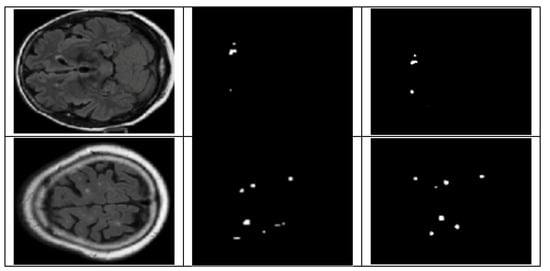

4.3. Detection and Classification

4.3.1. YOLOv8 Model for Detection and Classification